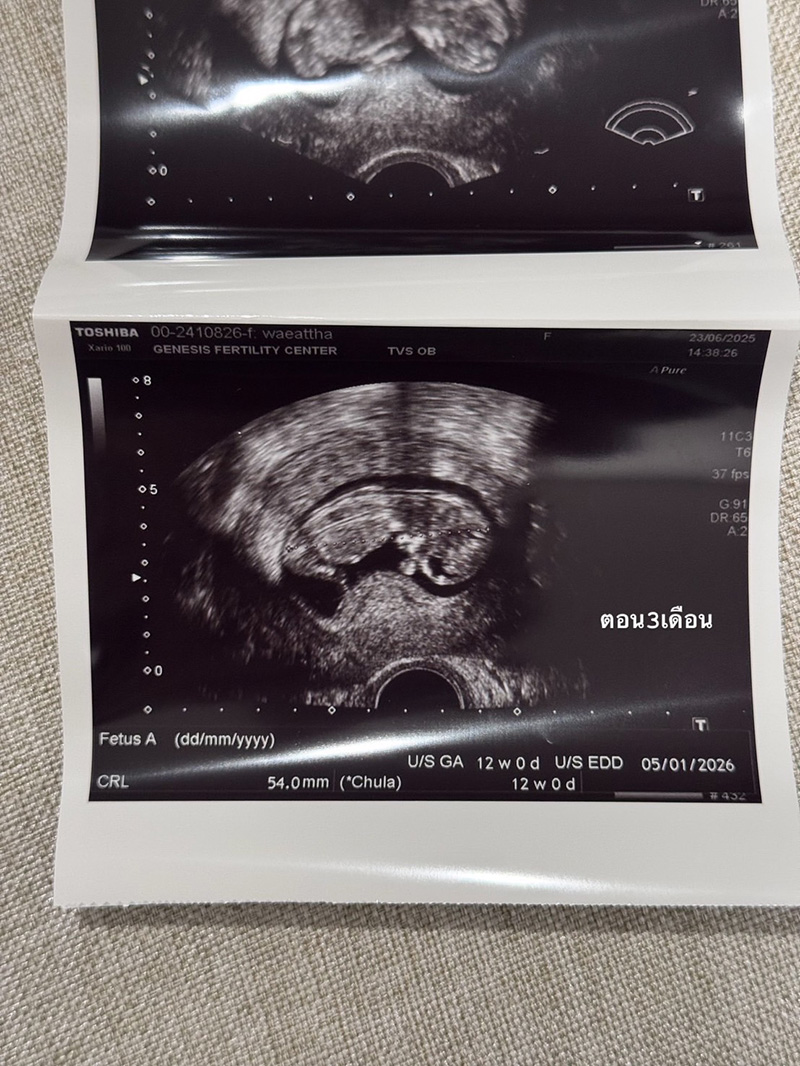

เนย วรัฐฐา ประกาศข่าวดีตั้งท้องลูกคนแรก ขอบคุณ GFC ที่สานฝันให้เป็นจริง หลังเจอภาวะโรคพันธุกรรมแฝง มีโอกาสสมบูรณ์ 25% เป็นเรื่องราวดี ๆ ให้แฟน ๆ ได้เข้ามาร่วมแสดงความยินดีกันอย่างล้นหลาม สำหรับ เนย วรัฐฐา หลังจากที่ได้เข้ามาปรึกษากับทาง GFC (Genesis Fertility Center) หนึ่งในผู้นำด้านการรักษาผู้มีบุตรยาก จากความใส่ใจในความสำเร็จที่พร้อมเติมเต็มความฝันให้ทุกครอบครัวเสมอได้ช่วยสานฝันให้ เนย วรัฐฐาเป็นความจริง โดยล่าสุด ว่าที่คุณแม่เนยได้โพสต์รูปถือรูปอัลตราซาวด์ลูกคนแรกพร้อมข้อความที่อ่านแล้วต้องยิ้มตาม แคปชั่นมีดังนี้ ช่วงนี้หาย ๆ ไปเพราะว่าเนยมีน้องแล้ว ในรูปคือประมาณ 3 เดือนตอนนี้ก็เกือบจะ 4 เดือนแล้ว ท้องป่องแล้ว ต้องบอกว่าจะมีลูกคนนึงไม่ง่ายเลยเข้าใจว่าตัวเองแข็งแรงสุขภาพดีมาก ดูแลตัวเองมาอย่างดีมาก ๆ อาหารการกินคือคลีน ไม่ดื่ม ออกกำลังกายสม่ำเสมอ นอนไม่ดึก แต่ปรากฏว่า เนยบ้ายบายน้องไปถึง 2 รอบ จนแปลกใจมากจริง ๆ เลยตัดสินใจไปหาคุณหมอมิงค์ ที่ @gfc.bangkok พอตรวจปรากฏว่า เนยละก็สามี มีโรคทางพันธุกรรมแฝงทั้งคู่ (เลยรู้สึกว่าก็โชคดีที่น้องบ้ายบายไปถึง 2 รอบเพราะถ้ารอดมาชีวิตก็คงลำบาก) โอกาสที่เด็กจะออกมาสมบูรณ์มีแค่ 25% เท่านั้น ซึ่ง % ที่เหลือคือเป็นโรคกับเป็นโรคแฝงแบบเนยที่ใช้ชีวิตปกติจนโตได้แต่เราก็จะมียีนที่ผิดปกติติดตัวส่งทอดไปสู่รุ่นอื่น ๆ ได้ ซึ่งเนยเลือกที่จะให้ลูกสมบูรณ์ 100% เลยดีกว่า เลยเริ่มทำ ICIS กับทางคลีนิค ทั้งคัดโครโมโซม ตรวจคัดโรค และหลังใส่ตัวอ่อนก็ทำ NIFTY อีก (คือต้องเพอร์เฟคละมั้ย 555) ต้องบอกว่าคุณหมอมิ้งค์ดูแลดีมาก ๆ ตั้งแต่วันแรกไปจนวันสุดท้ายของกระบวนการเลย รวมไปถึงพยาบาลทุกคนให้คำปรึกษาละรับฟังอารมณ์ของเราเป็นอย่างดี ส่วนขั้นตอนนั้นก็ใช้ความอดทน..55 ไม่เจ็บหรอกแต่จุกจิกเหลือเกินต้องกินยาสอดยาฉีดยาตัวเองให้ตรงเวลาเสมอไปทำงานทำอะไรต้องรีบกลับให้ทันเวลาฉีดยา สำหรับเนยเป็นการทำ ICIS ครั้งแรกแล้วก็ประสบความสำเร็จเลย ไม่ต้องทำหลาย ๆ รอบให้ท้อใจ ตอนนี้น้องสมบูรณ์แข็งแรงมากแค่ 3 เดือนก็ดิ้นเก่งซะแล้ว ต้องขอบคุณ GFC มาก ๆ ที่ทำให้ทุกอย่างราบรื่นจริง ๆ ส่วนใครที่แพลนจะมีลูกอยากบอกว่า ต่อให้จะอายุน้อยหรือแข็งแรงแค่ไหนแนะนำว่ามาตรวจเตรียมความพร้อมก่อนดีกว่า เพราะโรคแฝงมันไม่มีอาการ ตรวจสุขภาพปกติก็ไม่เจอ การมีธรรมชาติเลยบางทีมันก็ส่งผลต่อลูกของเรา ลูกเราอาจจะมีชีวิตเติบโตมาได้ แต่ถ้าเราคัดโครโมโซม คัดทุกอย่างให้สมบูรณ์เพื่อเป็นพื้นฐานการมีคุณภาพชีวิตที่ดีให้กับลูกได้มันก็น่าทำ จะได้ไม่ต้องมาคอยป่วย หรือมีอาการอะไรที่ไม่พึงประสงค์ แต่ถ้าลูกโตมาเที่ยวเก่งแบบพ่อ @ritkarchai ละป่วยแม่ก็แล้วแต่เลยจ้า 555